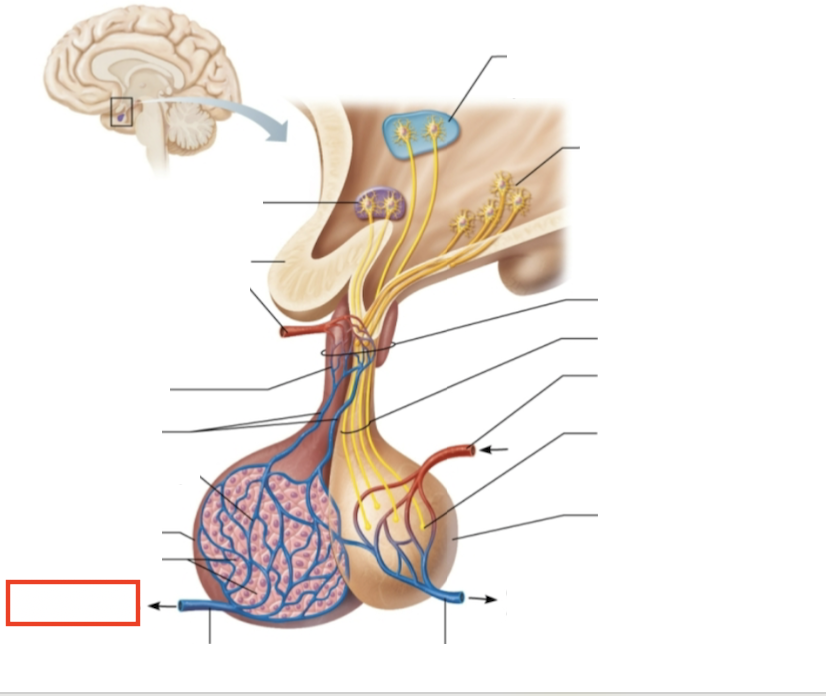

What structure is highlighted?

testes (male)

What are the target organs and effects of testosterone?

most cells of the body; promotes the maturation of the male reproductive organs, the development of secondary sex characteristics, sperm production, and sex drive

What hormone is produced by the testes?

testosterone

What stimulates testosterone production?

LH and FSH